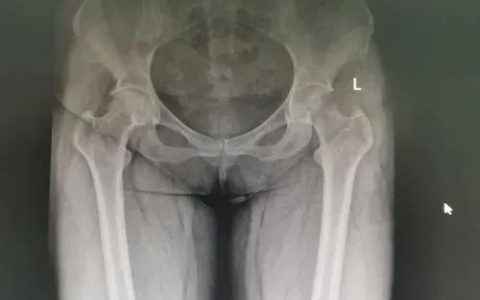

间充质干细胞移植治疗股骨头坏死11例报告

股骨头坏死为股骨头血液供应不足,导致缺血区骨细胞变性坏死。 坏死区的修复不充分,最终导致股骨头结构改变,股骨头塌陷,发生髋关节继发性骨关节炎,引起患者关节疼痛和功能障碍。 (资料图) 目前临床上治疗股骨…